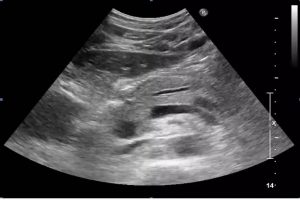

Diplomados en Ultrasonografía